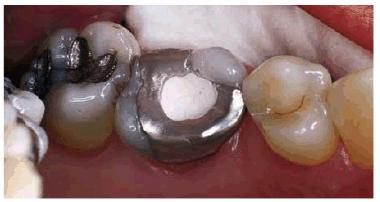

Figur 323s1823d e 18-12A: Periapical radiograph showing tooth #30 after successful root canal treatment.

Figur 323s1823d e 18-12B: Bitewing radiograph showing tooth #30 with amalgam core build-up completed. Note that the core material extends approximately 2 mm into the canal orifices for increased retention.